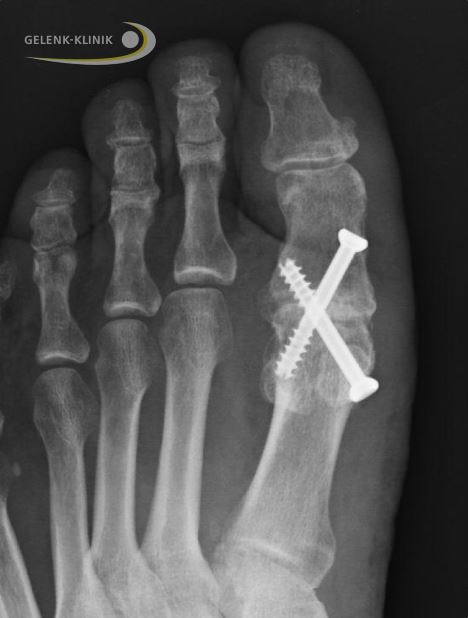

Bei der Arthrodese des Großzehengrundgelenks fusioniert der Chirurg den 1. Zehenstrahl mit dem 1. Zehenknochen durch Schrauben und Platten dauerhaft.

Die wichtigste Komplikation bei der Arthrodese ist das Ausbleiben der Knochenfusion, also die Bildung einer schmerzhaften Pseudarthrose (Falschgelenk) im versteiften Gelenk. Unter Einsatz von Platten gibt es evtl. weniger Pseudarthrosen, als wenn das Gelenk nur versteift wird.

Um ein gutes, alltagstaugliches Ergebnis zu erzielen, muss das Großzehengelenk in einem bestimmten Winkel versteift werden: 15°–40° in Dorsalextension (Beugung nach oben) und etwa 15° valgus (horizontal in Richtung Fußaußenkante geneigt).